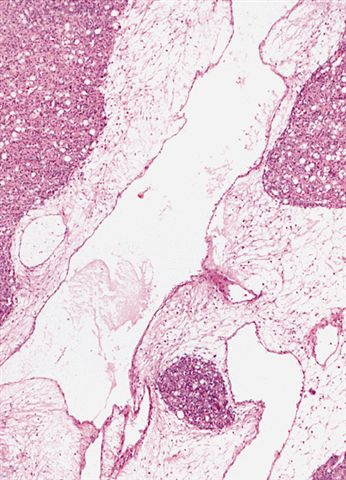

- Low grade

- Paucicellular with monomorphic, stellate or fusiform shaped cells without atypia; striking in their blandness, so much so that any significant pleomorphism should cause one to pause

- Prominent plexiform vasculature (delicate thin walled arborizing and curving capillaries that form a network reminiscent of chicken wire fencing)

- These are striking because of the overall background paucicellularity and are still present in high grade tumors but are much less obvious

- Numerous signet ring lipoblasts, particularly at periphery of lobules

- This imparts a lipoblastoma-like appearance (see Differential diagnosis)

- Mucoid matrix is rich in hyaluronic acid that may form large mucoid pools (so called pulmonary edema pattern)

- Will be positive for stromal mucin stains such as Alcian blue (see Microscopic (histologic) images)

The microscopic image above depicts the histologic appearance of a soft tissue mass resected from the thigh of a 37 year old man and is representative of the entire lesion. Which of the following is true regarding the diagnosis?

D. Majority of cases harbor t(12;16) FUS::DDIT3 gene fusion. The microscopic image depicts a low grade myxoid liposarcoma characterized by a proliferation of bland stellate tumor cells embedded in a myxoid matrix with a prominent plexiform capillary network and scattered signet ring lipoblasts. There is no mitotic activity or pleomorphism. The majority of cases of myxoid liposarcoma harbor a t(12;16) FUS::DDIT3 gene fusion. Answers B and C are incorrect because the t(9;22) EWSR1::NR4A3 gene fusion is characteristic of extraskeletal myxoid chondrosarcoma and the t(7;16) FUS::CREB3L2 gene fusion is characteristic of low grade fibromyxoid sarcoma. Answer E is incorrect because classification of myxoid liposarcoma as high grade requires > 5% of the sampled lesion to consist of a hypercellular round cell component according to the WHO. Cases with borderline round cell component (< 5%) are regarded as having areas of transition, a designation of unclear diagnostic significance. Answer A is incorrect because immunohistochemistry for MDM2 is negative in myxoid liposarcomas.